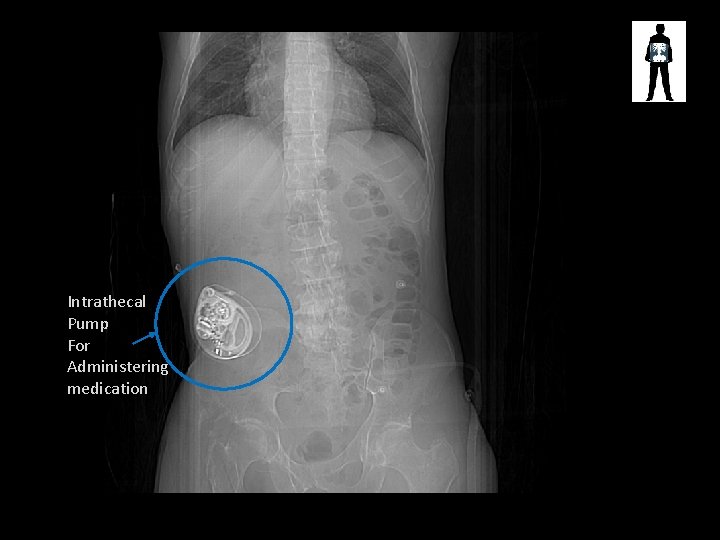

Intrathecal Pump For Administering medication

Intrathecal pump • Small, surgically inserted pump • Used to direct small volumes of medication around the intrathecal space, around the spinal cord • Commonly used for – Chronic pain – Spasticity or displegia